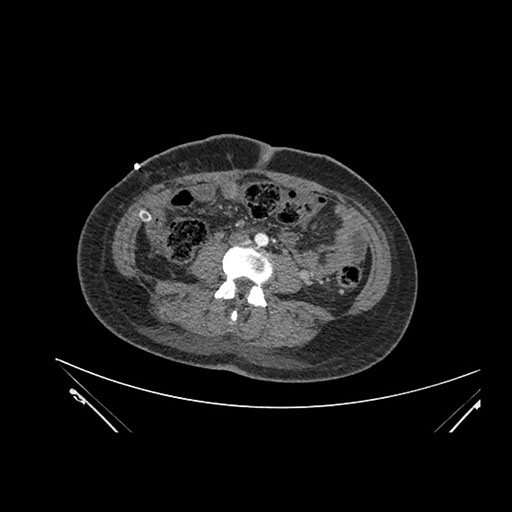

Axial Arterial

Imaging analysis

Based on initial findings, which issue(s) would you be most concerned about?